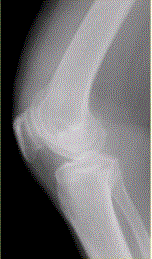

问题 患者女,54岁,右膝关节痛。实验室检查:类风湿因子阳性,除外膝关节类风湿性关节炎。X线检查结果如下图。 X线平片表现不包括

选项 A.关节边缘骨赘形成 B.关节边缘骨侵蚀 C.关节间隙不均匀变窄 D.关节囊肿胀 E.股骨内侧髁关节面下局限性硬化

答案 B